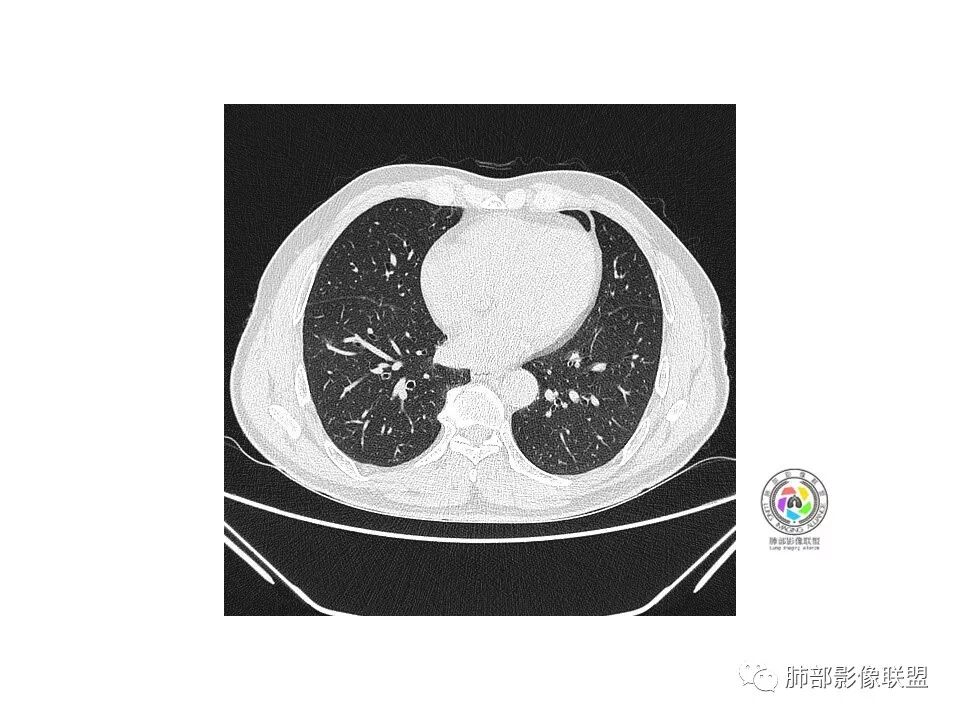

老年男性,右下叶孤立ggo,先抗炎2-3周复查,无变化→切,小了→炎性

40岁以上男性,孤立混合磨玻璃,边界清楚,分叶,胸膜凹陷,血管集束、穿行,考虑腺癌。

右肺下叶孤立混合磨玻璃结节,隐约细小毛刺,似有月牙铲,胸膜稍牵拉,考虑MIA(微浸润腺癌)可能,常规飞一下。

先按临床常规思路抗炎治疗,没有吸收变化后,根据病人意愿可以选择随访观察或者直接手术,腺癌还是得常规考虑

彭君:

右肺下叶前基底段混合磨玻璃密度结节 边缘见月牙铲 部分边缘清 部分似清非清 远端见磨玻璃片影,炎性和粘液腺癌鉴别 先抗炎复查

病史:老年男性,咳、痰三天;

1.纵膈窗未显示;水平裂有轻微凹陷,那个条索影,有形成机理进一步分析;前方那个血管,可能是肺动脉?有一定弯曲度(向病灶),后方这个是肺静脉;3个小叶凹,有可能,受到阻挡,邻近小血管有相应改变;薄层那个细小血管有弯曲,形成部分实性;

2.大小:估计15*10mm左右;

3.CT值:混杂,有些偏高;

4.周围小血管,有形成毛刺趋势;

5.血管:如上述;

6.胸膜和叶间裂:有轻微牵拉;

诊断:浸润性腺癌;鉴别:炎性结节;

处理:炎标、肿标、病史、职业史、抽烟史,既往胸部检查;